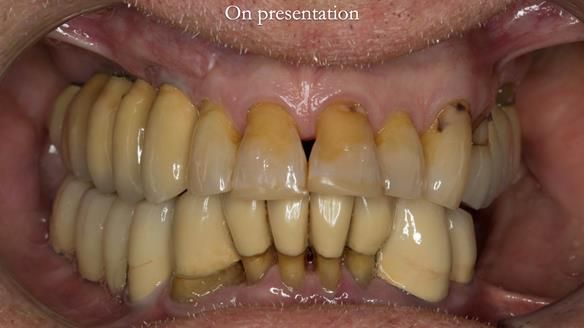

Ken – going downhill, first class

I first met Ken in 2015, when he was 80 years old.

He had lived in both the UK and the USA, spending many years in Florida, where he received extensive dental and periodontal care.

The starting point

We began with the lower jaw.

Final thoughts

This case was always about function, not aesthetics.

Ken’s teeth were never going to look perfect.

There were stained composites, old restorations, and obvious wear.

That was accepted from the outset.